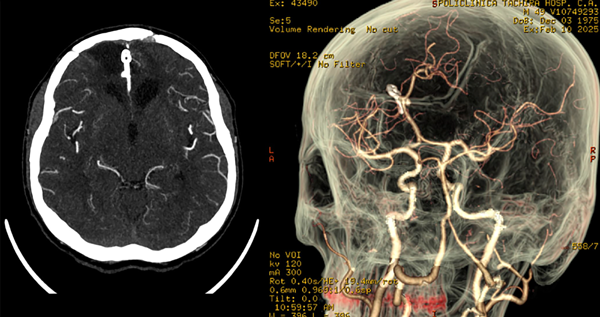

Posteriormente es trasladado a terapia intensiva intubado donde se mantiene bajo sedoanalgesia en infusión por 24 horas y, tras reversión, se evidencia Glasgow 11/15 (respuesta verbal: 4, respuesta motora: 6), sin déficit neurológico aparente. Se retira drenaje subcutáneo a las 48 horas postoperatorias. Se indica tomografía cerebral simple (Figura 3) con buen control de evacuación de las colecciones hemáticas, y la AngioTC con correcta exclusión del aneurisma (Figura 4). El paciente tiene una óptima evolución.

Figura 3. Tomografía cerebral simple. En cortes axial, coronal y sagital se muestra: cuerpo hiperdenso en fisura interhemisférica que genera discreto efecto Hounsfield correspondiente con clip simple de palas rectas normoposicionado. Áreas de encefalomalacia bifrontal. Cisternas de la base libres y permeables, sistema ventricular de topografía normal, preservación de los elementos de la línea media, presencia de surcos y circunvoluciones, adecuada diferenciación sustancia gris-blanca y corticosubcortical. Defecto de craneotomía.

Figura 4. Angiotomografía cerebral. En corte contrastado axial se observa: cuerpo hiperdenso en fisura interhemisférica que genera discreto efecto Hounsfield correspondiente con clip simple de palas rectas normoposicionado, área de encefalomalacia orbitofrontal de predominio izquierdo. En reconstrucción 3D: exclusión de la circulación de aneurisma de ACAa, clip normoposicionado, preservación de ramos vasculares distales.